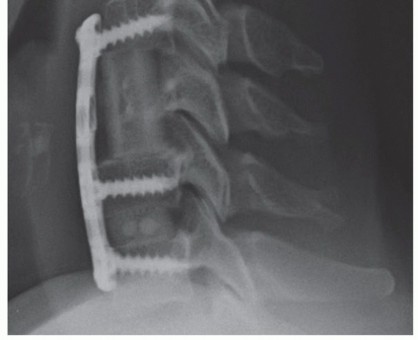

### FIG 3 • Hybrid constructs. This patient had retrovertebral cord compression behind C5 and disc-based compression at C6-C7. Rather than doing a two-level corpectomy of both C5 and C6, a corpectomy-discectomy construct allows for a shorter strut graft and intermediate points of screw fixation into C6. Exacerbation of axial neck pain can occur after laminoplasty in those who have significant complaints preoperatively, although it rarely becomes of significance in those who have little to no axial pain preoperatively. Also, adequate decompression may not occur after laminoplasty in those with kyphosis, as cord driftback away from anterior compressive lesions is unreliable in this setting. ##